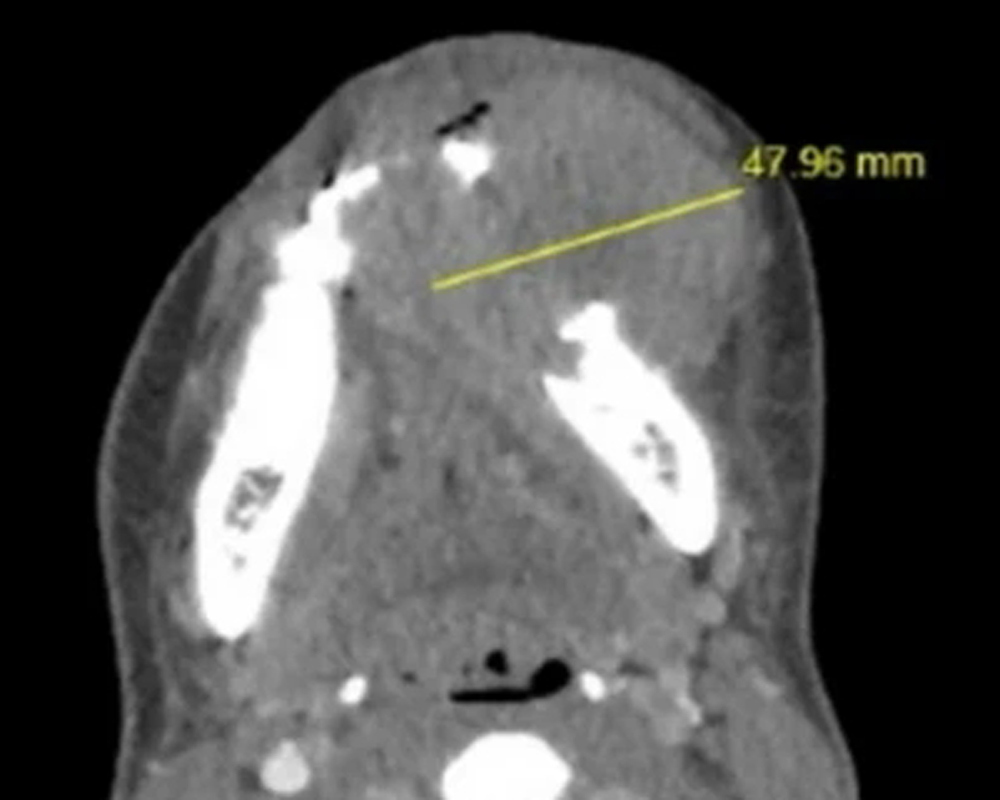

Characterization of CD8 + & CD68 + Microenvironment & PDL1 Expression in HPV-related Multiphenotypic Sinonasal Carcinoma

Silva de Araújo, Gonçalves de Paiva, Lima Fernandes, et al.